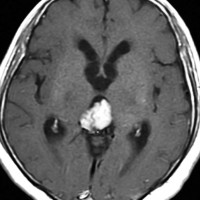

成人男性が早朝の頭痛で発症しました。閉塞性水頭症になっているので第3脳室開窓術が行なわれてから紹介されてきました。開頭手術で全摘出して,病理が PPTID グレード3でしたので,脳脊髄照射 24Gy/12fr と腫瘍局所照射 54Gy/27fr をしました。